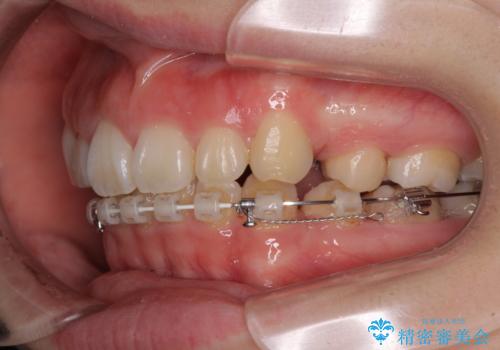

- ハーフリンガル

目立たない装置が希望であったため、上顎が裏側装置である、ハーフリンガル装置を選択されました。

非常に大きな虫歯のあった下顎大臼歯は、根管治療を行い、矯正治療後にオールセラミッククラウンにて補綴治療を行いました。

当初予定では3年以上かかるとお伝えしておりましたが、スムーズに歯列が整い、2年強で終了することができました。